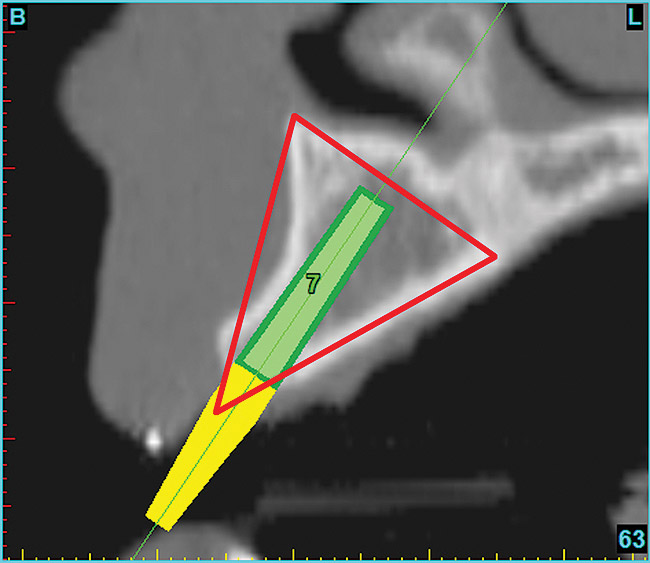

Using the interactive treatment-planning software application, the scan data was assimilated and both potential lateral incisor implant receptor sites were evaluated. It is a combination of the data and the methodology used to interpret the data that is the basis for defining a new paradigm in diagnosis and treatment planning. Proper evaluation of these images and correct use of the interactive treatment planning software tools is essential in creating a decision tree of treatment options. First, the data from the scan was reformatted into panoramic, axial, and cross-sectional images. The undistorted cross-sectional images revealed the residual alveolar bone in the area of the right lateral incisor. Then, a simulated schematic implant was placed within the bone with an abutment extension to help visualize the connection to the restorative position of the tooth (Figure 6). The Triangle of Bone® (TOB), a concept developed by the author to analyze bone quality, quantity, and disposition at prospective dental implant sites using CBCT scans, aided in determining available bone volume by defining a “zone” for proper implant placement18,19 (Figure 7).

After reviewing the CT data and the decision tree, the bone within the “zone” of the TOB was evaluated and found to be satisfactory for implant placement. Because the goal of implant dentistry is not the implant but the tooth that is placed, true restorative-driven implant dentistry must begin with the assumption that the implant position should remain consistent with the tooth it is replacing, and the final implant-supported restoration.12,22-26 The TOB aids the clinician in understanding the link between the implant position and the desired restorative goal. The base of the geometric shaped “zone” is visualized by starting at the widest area of alveolar bone facially and superiorly. The apex of the triangle is positioned to bisect the alveolar crest (Figure 7). The TOB, the overlay in the cross-sectional image, reveals whether adequate bone is available for implant placement. It also helps to identify concave facial bone defects, and accurately determine the width of bone at the crest. The author recommends using an interactive software application that provides the necessary measurement tools to accurately assess the bone anatomy.

Figure 7  SOFTWARE IMAGING The determination of the "zone" for proper placement.

Figure 7